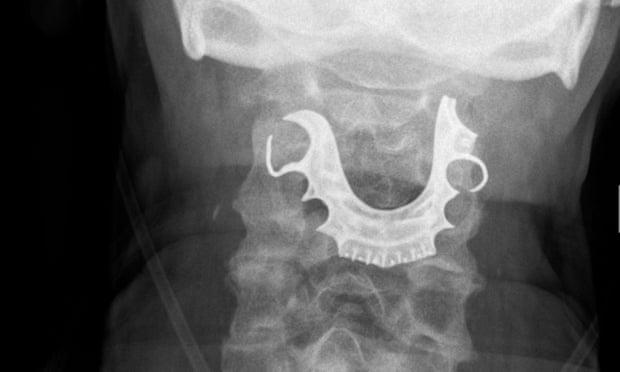

最终,诊断发现了在他的声带上有一个半圆形的物体,其引起了内部的水泡和肿胀。这名老人随后被送往外科手术摘除假牙,他在医院又住了六天。在接下来的一个月里,他多次出现并发症,直到最终痊愈。